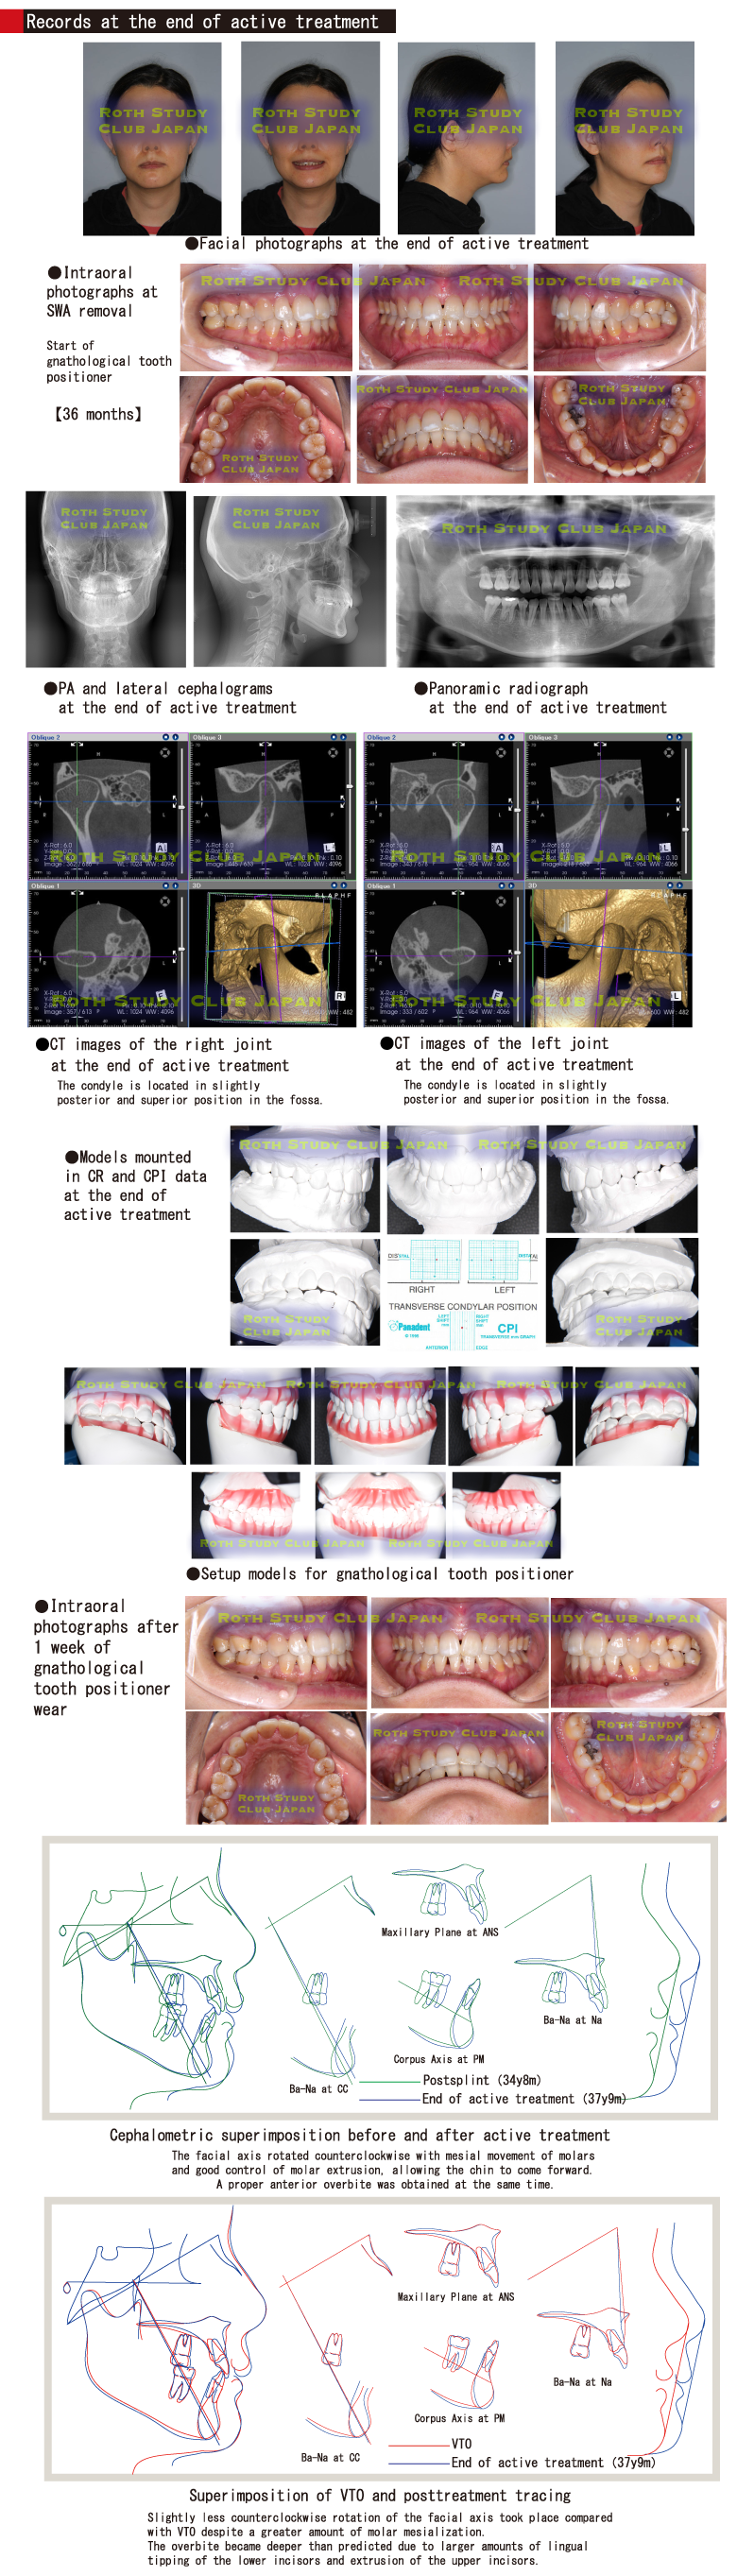

Records at the end of active treatment